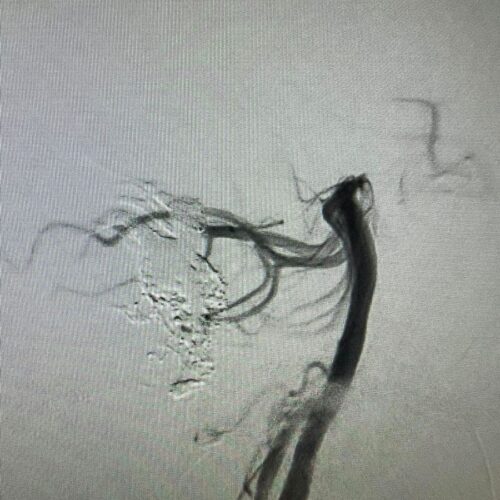

Δια ζώσης συμμετοχή των φοιτητών του Πανεπιστημίου Πατρών σε εξειδικευμένες τεχνικές ενδοαγγειακής αντιμετώπισης αγγειακών δυσπλασιών του κεντρικού νευρικού συστήματος.

Στην επέμβαση συμμετείχαν ο Καθηγητής Ενδοαγγειακής Νευροχειρουργικής Κος Β. Παναγιωτόπουλος, ο Καθηγητής Επεμβατικής Νευροακτινολογίας κος Π. Ζαμπάκης, ο επιμελητής επεμβατικής ακτινολογίας κος Μ. Θεοφάνης και ο αναισθησιολόγος κ. Γούδας.